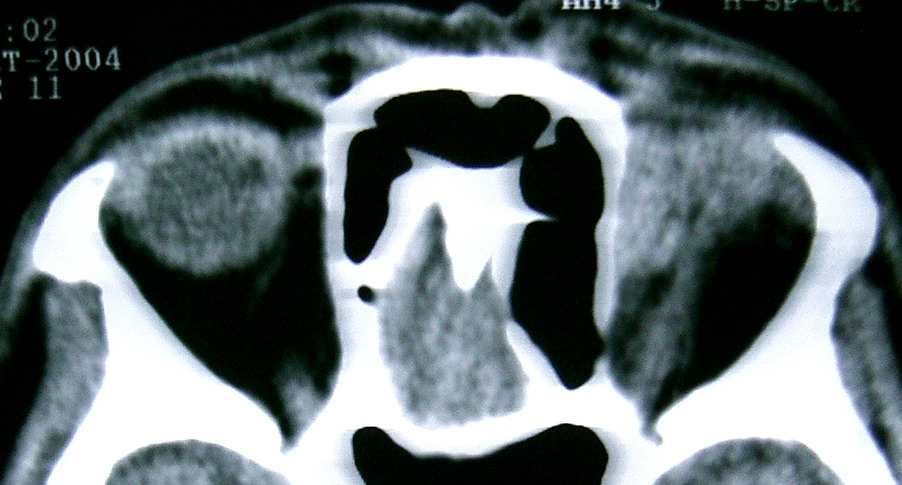

2,上眼眶CT示:左眼眶内肿物

此主题相关图片如下:

按此在新窗口浏览图片

眼眶冠扫,平扫CT:

左眼球内上方可见不规则软组织块影,大小约2.5*1.0CM,与邻近组织分界不清,相邻之内直肌、上直肌增粗,眼环正常,眶壁骨质无破坏,左上颌窦底部可见粘膜增厚,其余副鼻窦未见异常。

IMP:1,左眼眶肿物;2,左上颌窦炎